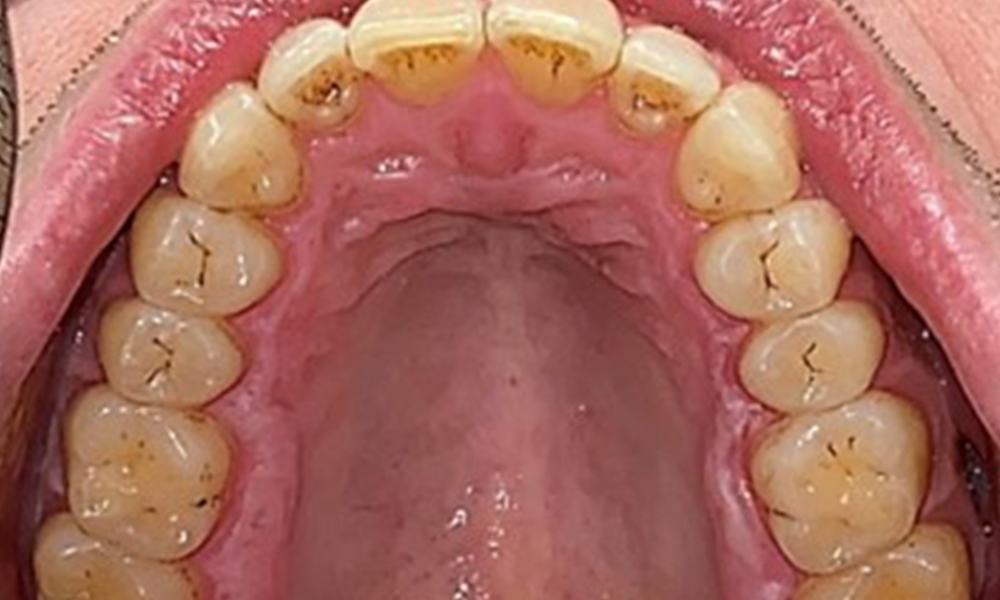

Le patient a une dentition complète avec un total de 28 dents. Il y avait des érosions et des attritions notables. (Fig. 4, Fig. 5). En raison du bruxisme, le patient a porté pendant de nombreuses années une attelle avec une gouttière ajustée la nuit. Les érosions ont été causées par une consommation prolongée de boissons isotoniques. Aucune perte d'os parodontal ou carie active n'a été observée.